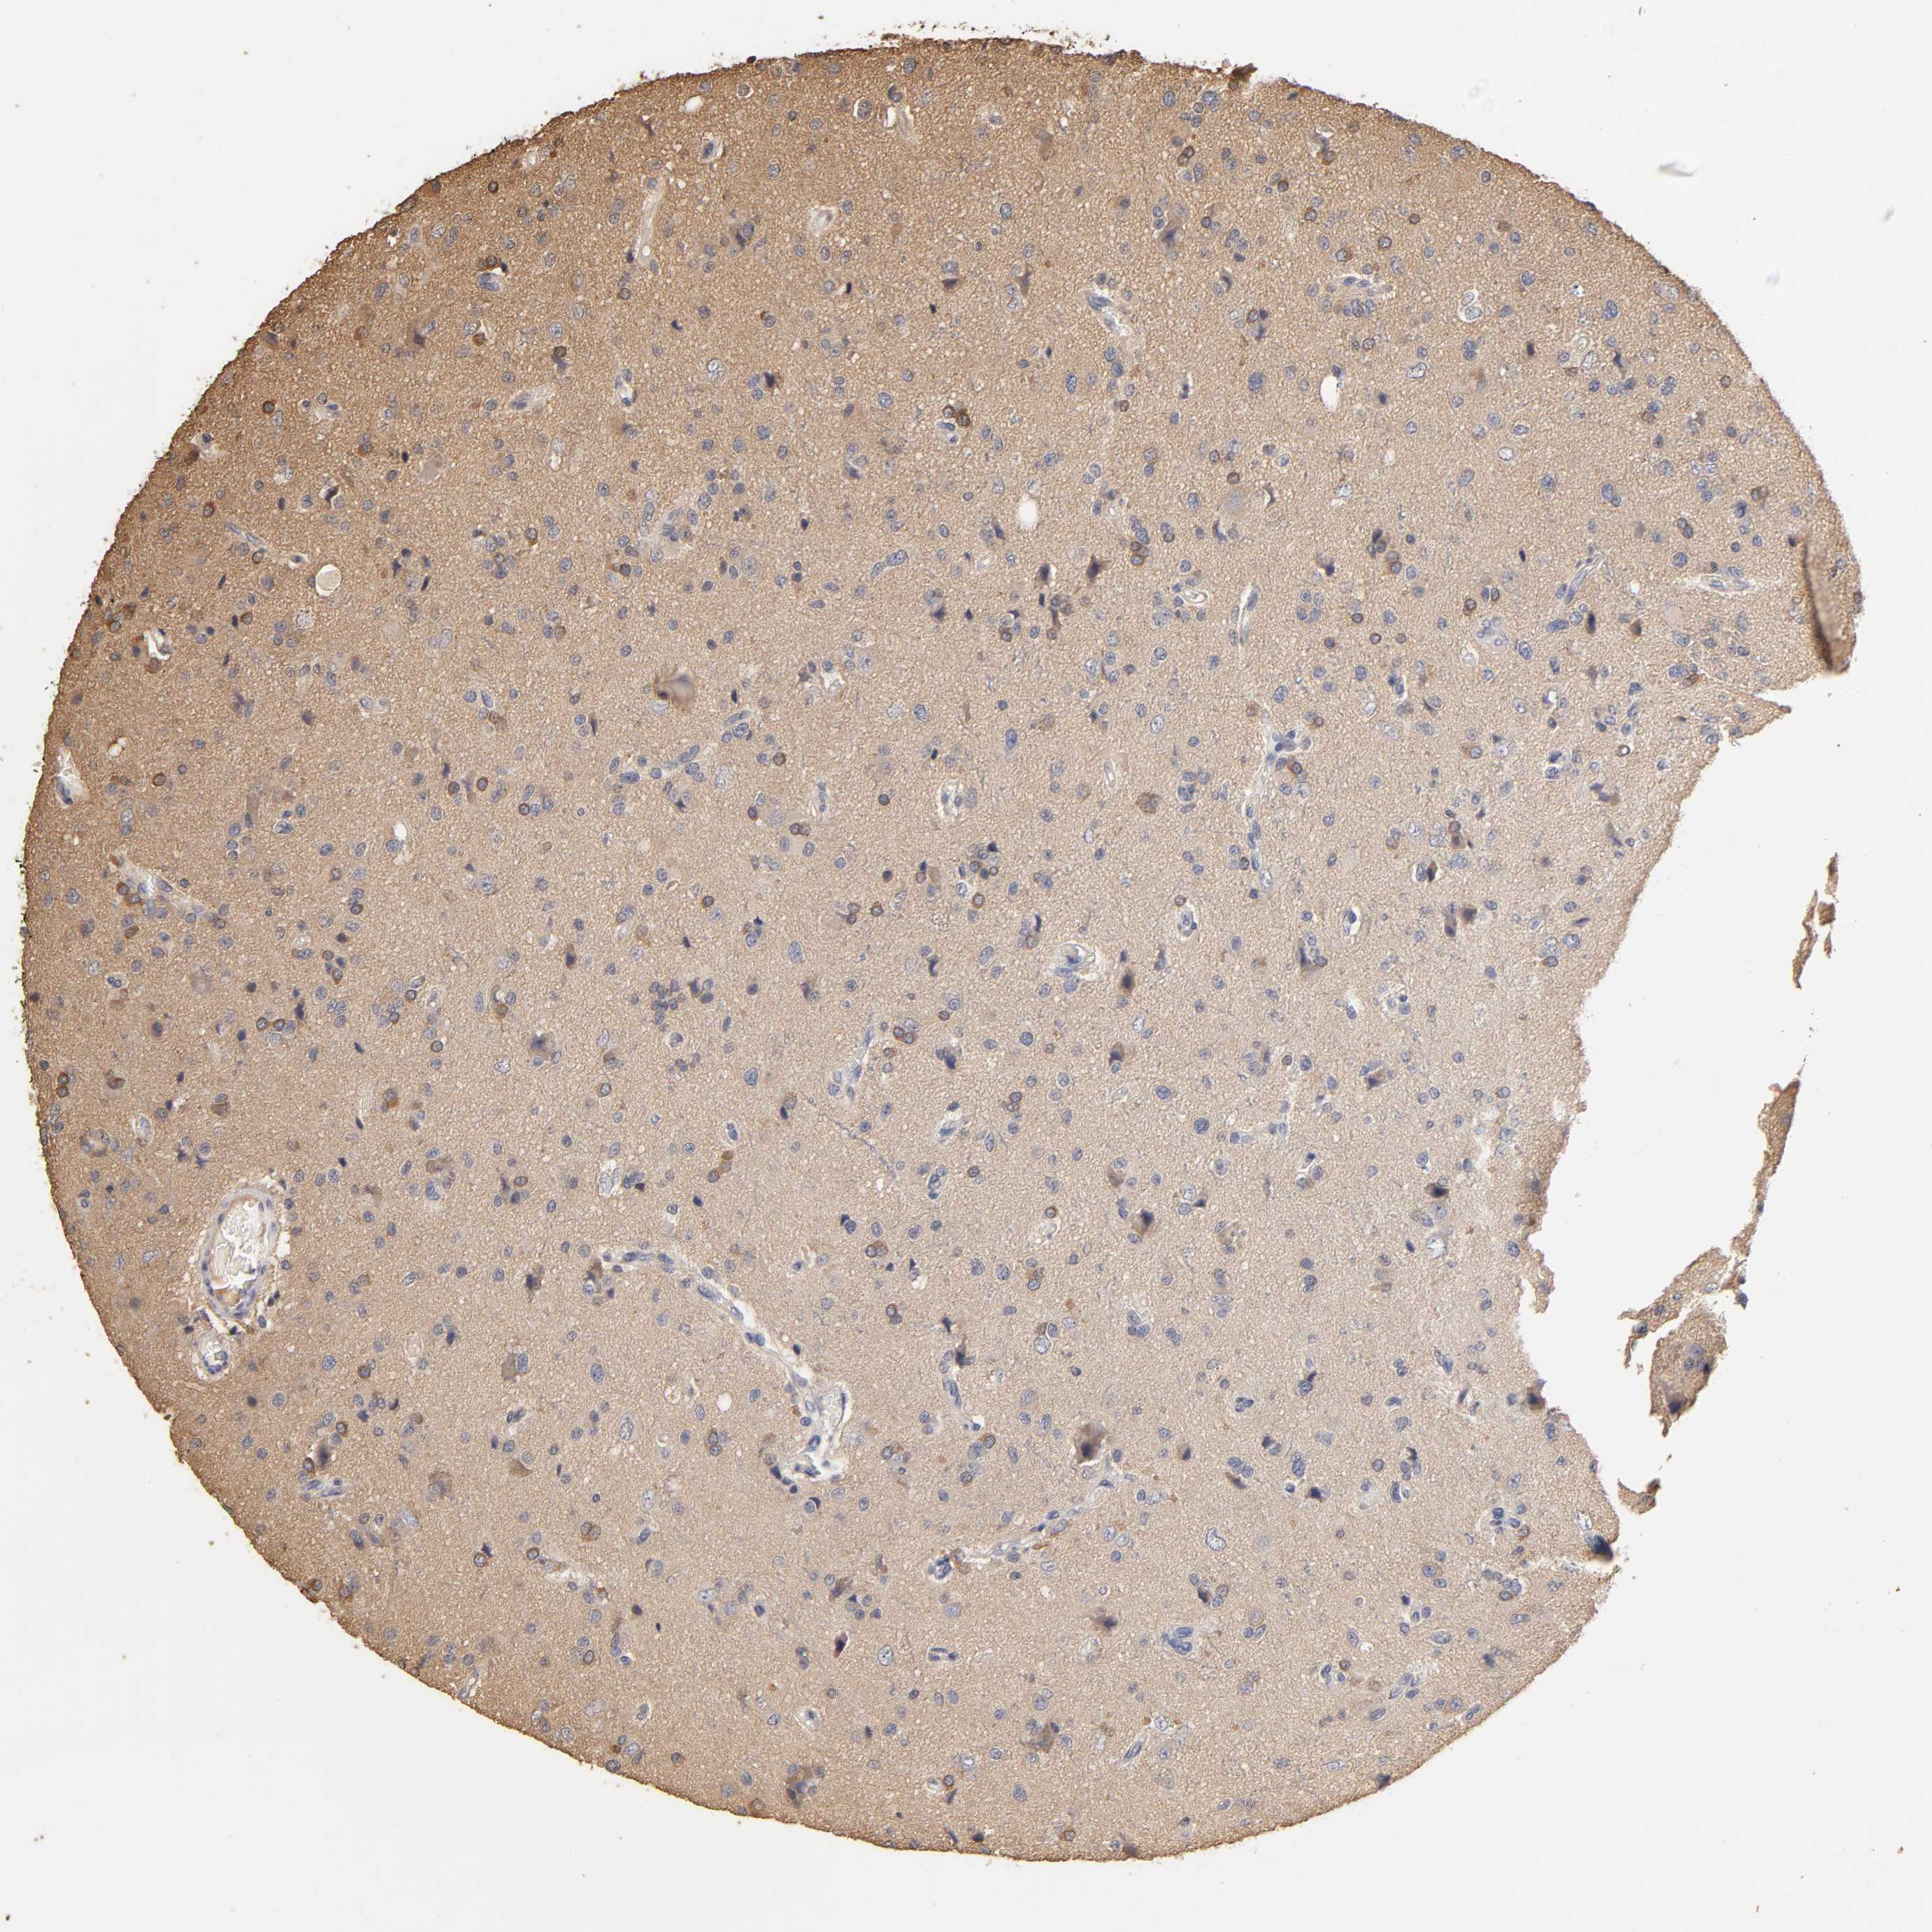

GLIOMA - Protein expressioni

A mouse-over function shows sample information and annotation data. Click on an image to view it in a full screen mode. Samples can be filtered based on level of antibody staining by selecting one or several of the following categories: high, medium, low and not detected. The assay and annotation is described here.

Note that samples used for immunohistochemistry by the Human Protein Atlas do not correspond to samples in the TCGA dataset.

Antibody stainingi

Antibody staining in the annotated cell types in the current human tissue is reported as not detected, low, medium, or high, based on conventional immunohistochemistry profiling in selected tissues. This score is based on the combination of the staining intensity and fraction of stained cells.

Each image is clickable and will lead to virtual microscopy that enables deeper exploration of all samples and also displays staining intensity scores, fraction scores and subcellular localization as well as patient and tissue information for each sample.

Antibody HPA003903

Antibody HPA072756

Antibody CAB026000

Staining

High

Medium

Low

Not detected

Intensity

Strong

Moderate

Weak

Negative

Quantity

>75%

75%-25%

<25%

None

Location

Nuclear

Cytoplasmic/membranous

Cytoplasmic/membranous,nuclear

Glioma, malignant, High grade

Glioma, malignant, NOS

Glioma, malignant, Low grade